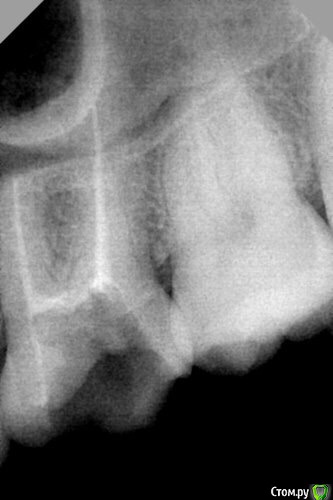

dr.Dre Опубликовано 13 августа, 2015 Поделиться Опубликовано 13 августа, 2015 Добрый день верхний 6 зуб,запломбировал 3 канала а на рентгене видны 2,может такое быть что МВ1 слился з небным,только начинаю работать Ссылка на комментарий

Бардо Опубликовано 13 августа, 2015 Поделиться Опубликовано 13 августа, 2015 может такое быть что МВ1 слился з небным У вас, например, так и произошло. Только дистальный, а не мб1 все же наверное. Чем пломбировали, как обрабатывали? Снимок без времяшки делали что-ли? Ссылка на комментарий

diesel87 Опубликовано 13 августа, 2015 Поделиться Опубликовано 13 августа, 2015 Метод одного штифта не по протоколу, хотя смотря какой протокол у вас. На снимке же четко видно периодонталку обоих корней, маленький дистальный на большом небном. 1 Ссылка на комментарий

diesel87 Опубликовано 13 августа, 2015 Поделиться Опубликовано 13 августа, 2015 Вы скажите пожалуйста там все каналы запломбированы?3 из 4-ех 3 Ссылка на комментарий

dr.Dre Опубликовано 13 августа, 2015 Автор Поделиться Опубликовано 13 августа, 2015 3 из 4-ех4 не нашел Ссылка на комментарий

St. Опубликовано 14 августа, 2015 Поделиться Опубликовано 14 августа, 2015 Они просто на снимке наложены друг на друга верно? Да, старайтесь делать снимки, чтобы было видно все каналы. Можно делать несколько снимков.Метод одного штифта это плохо , поскольку в большинстве случаев так не получается герметично и полностью заполнить канал. Переходите лучше на латеральную компакцию. Ссылка на комментарий

diesel87 Опубликовано 14 августа, 2015 Поделиться Опубликовано 14 августа, 2015 Да ладно, может он в 10 или сколько там % счастливых 3-канальных входит.Так mb2 четко просматривается на снимке, к бабке не ходи. Ссылка на комментарий